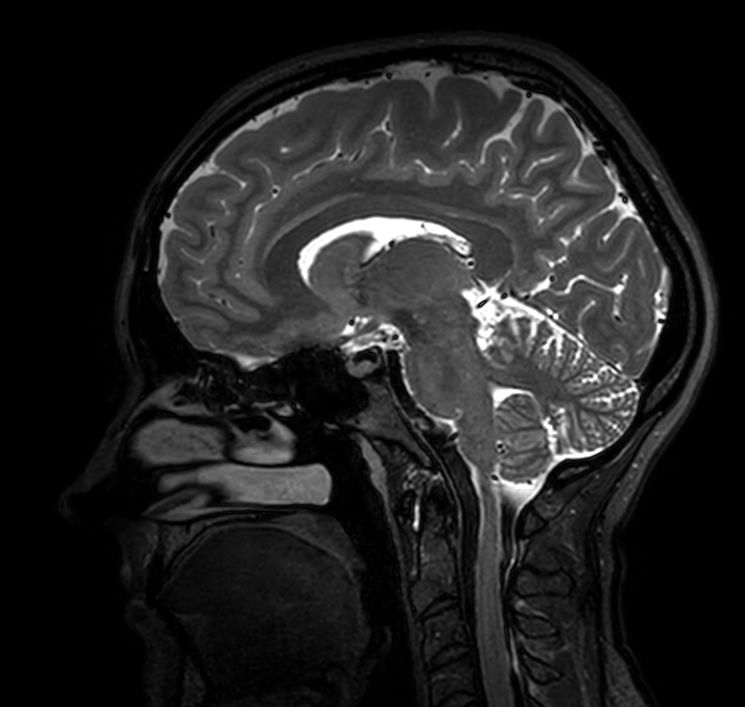

Sagittal 3D T2w TSE

-

3D T2w TSE (Axial reformat)